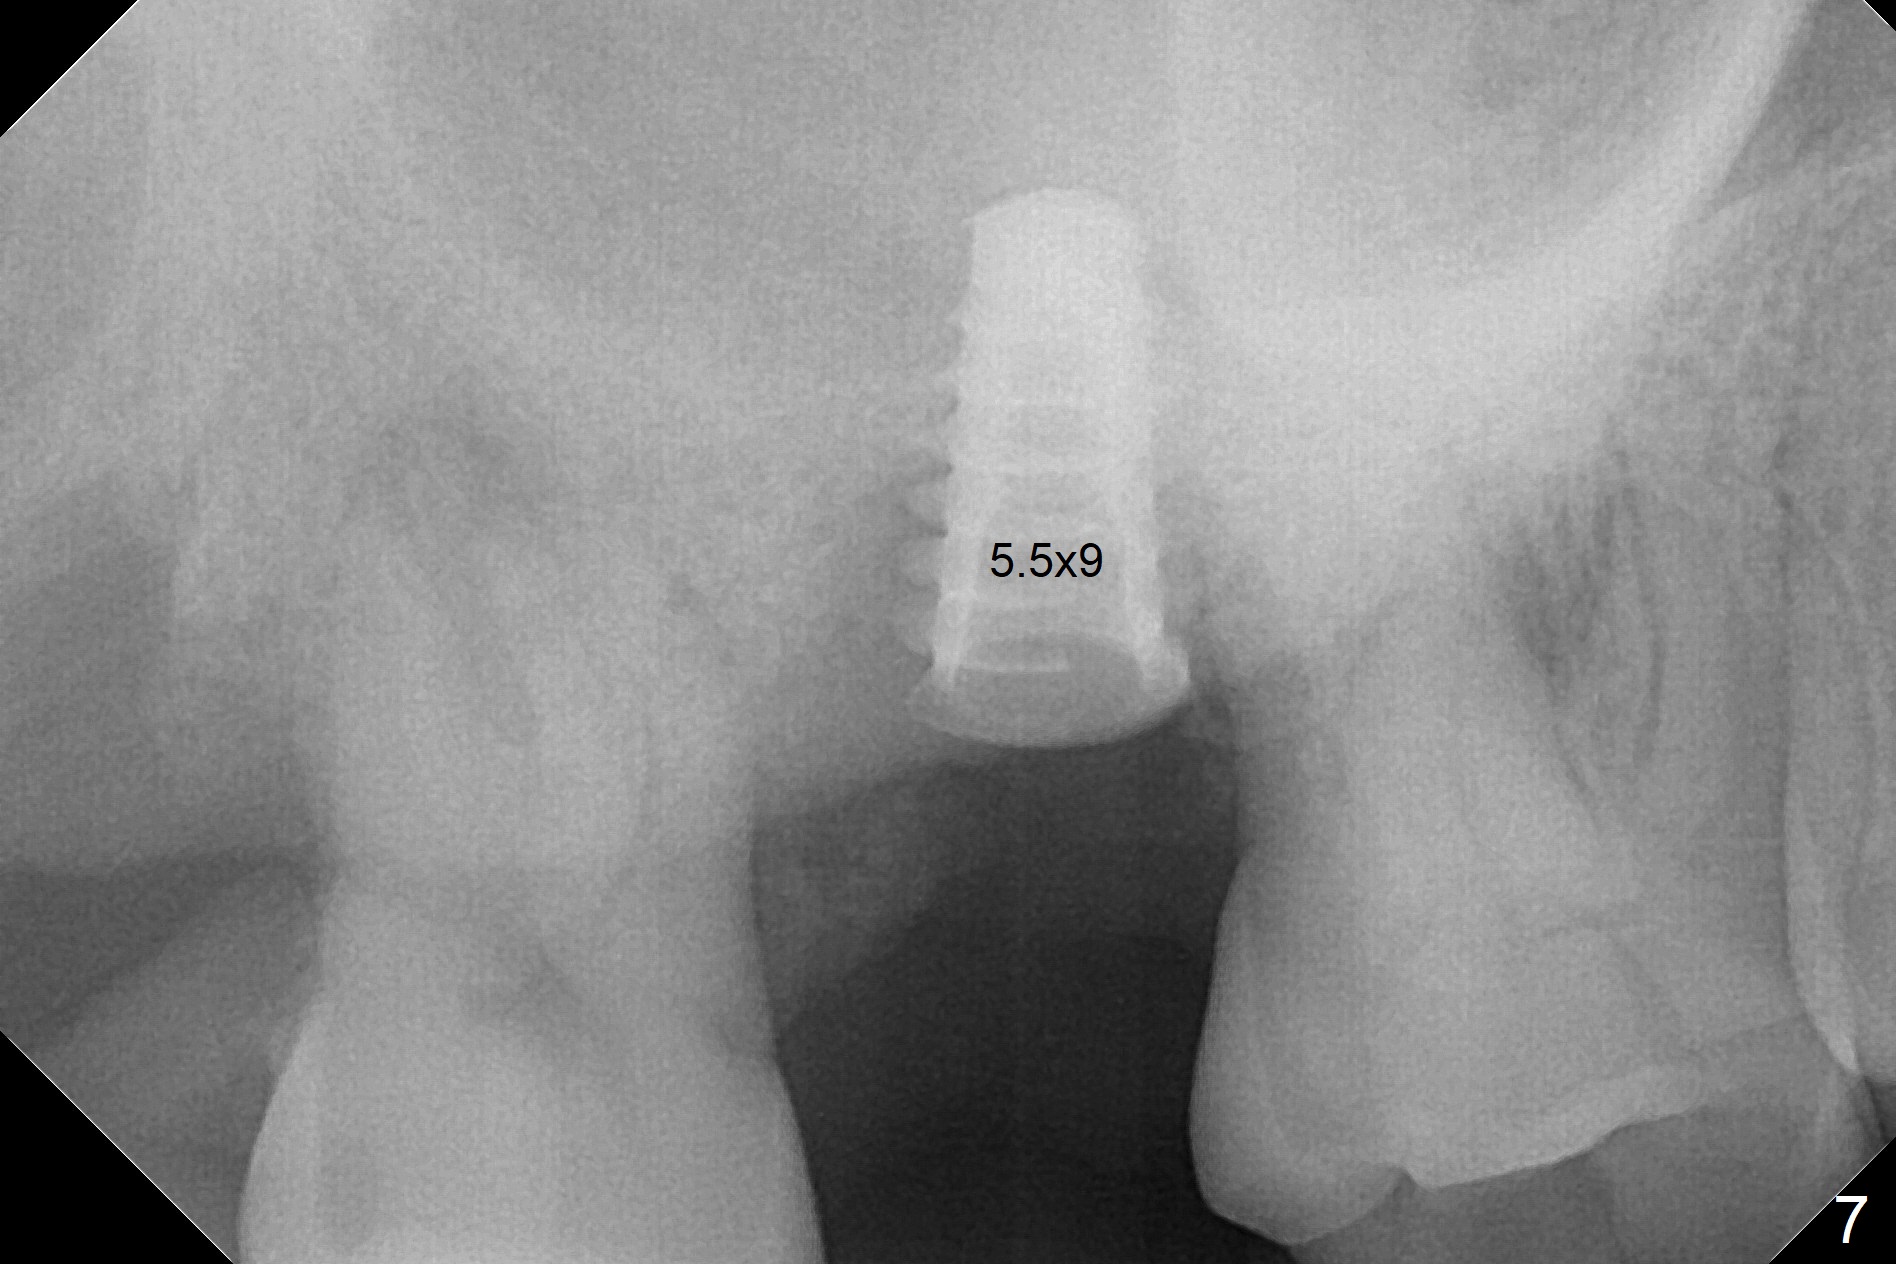

When the 59-year-old man returns for #24 implant placement, the tooth #2 is found to have crack (Fig.1,2 arrowheads), associated with buccal and palatal fistulae (*) and loss of amalgam (Fig.4 *). Abundant granulation tissue is attached to the roots of the affected tooth (Fig.3), indicating severe bone loss. There is a plateau associated with the septum and buccal sockets, which is the site of osteotomy. Magic split and 3 and 3.8 mm Magic Expanders are used to initiate osteotomy. After use of 4.3 mm Magic Drill for about 3 mm, Osteogen plug and allograft are used for sinus lift, followed by insertion of a 4.5x11 mm dummy implant (Fig.5). When a 5.5x9 mm dummy implant is placed with stability, it appears to be seated cervical (Fig.6,7). When a 6x9 mm IBS implant (definitive) is placed with a 6.5x5.5(4) mm abutment, they are seated too deep for provisional (Fig.8). The implant/abutment are removed and replaced by a 6.5x11 mm one in a shallower position; after trimming the same abutment as mentioned above (Fig.9), an immediate provisional is fabricated to keep bone graft in place. Fabrication of Tap with soft tissue markers will reduce the chance of miscalculation and waste of implants. The coronal threads of the implant are covered with bone 6 months postop (Fig.10). One month later when a permanent crown tries in, the implant is found to be loose and tender. A healing abutment is placed. Six months later, the patient returns for crown retry-in. The tooth #1 seems to have shifted mesially (Fig.11 arrow). When the abutment is placed, the implant remains tender and loose. After implant removal with a wrench, there is no granulation tissue or bony defect, including the intact sinus floor (Fig.12 <). Since the tooth #1 has deep periodontal pockets and mobility, the tooth is extracted with abundant granulation tissue. After debridement, Osteogen plug is placed in the socket of #1, while Vanilla graft is placed at the site of #2 (Fig.13 *). Three weeks later, the socket of #2 heals with exposure of Osteogen plug (Fig.14 (B: buccal)).